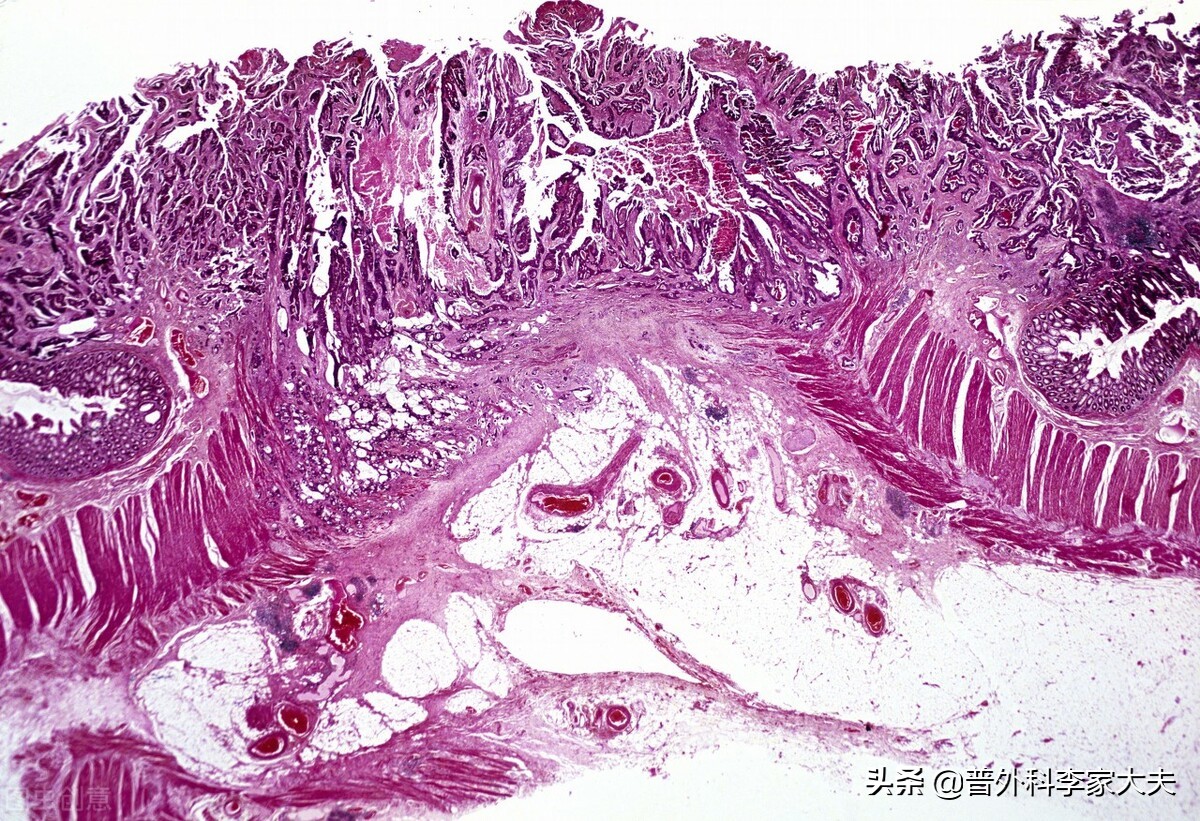

结肠癌